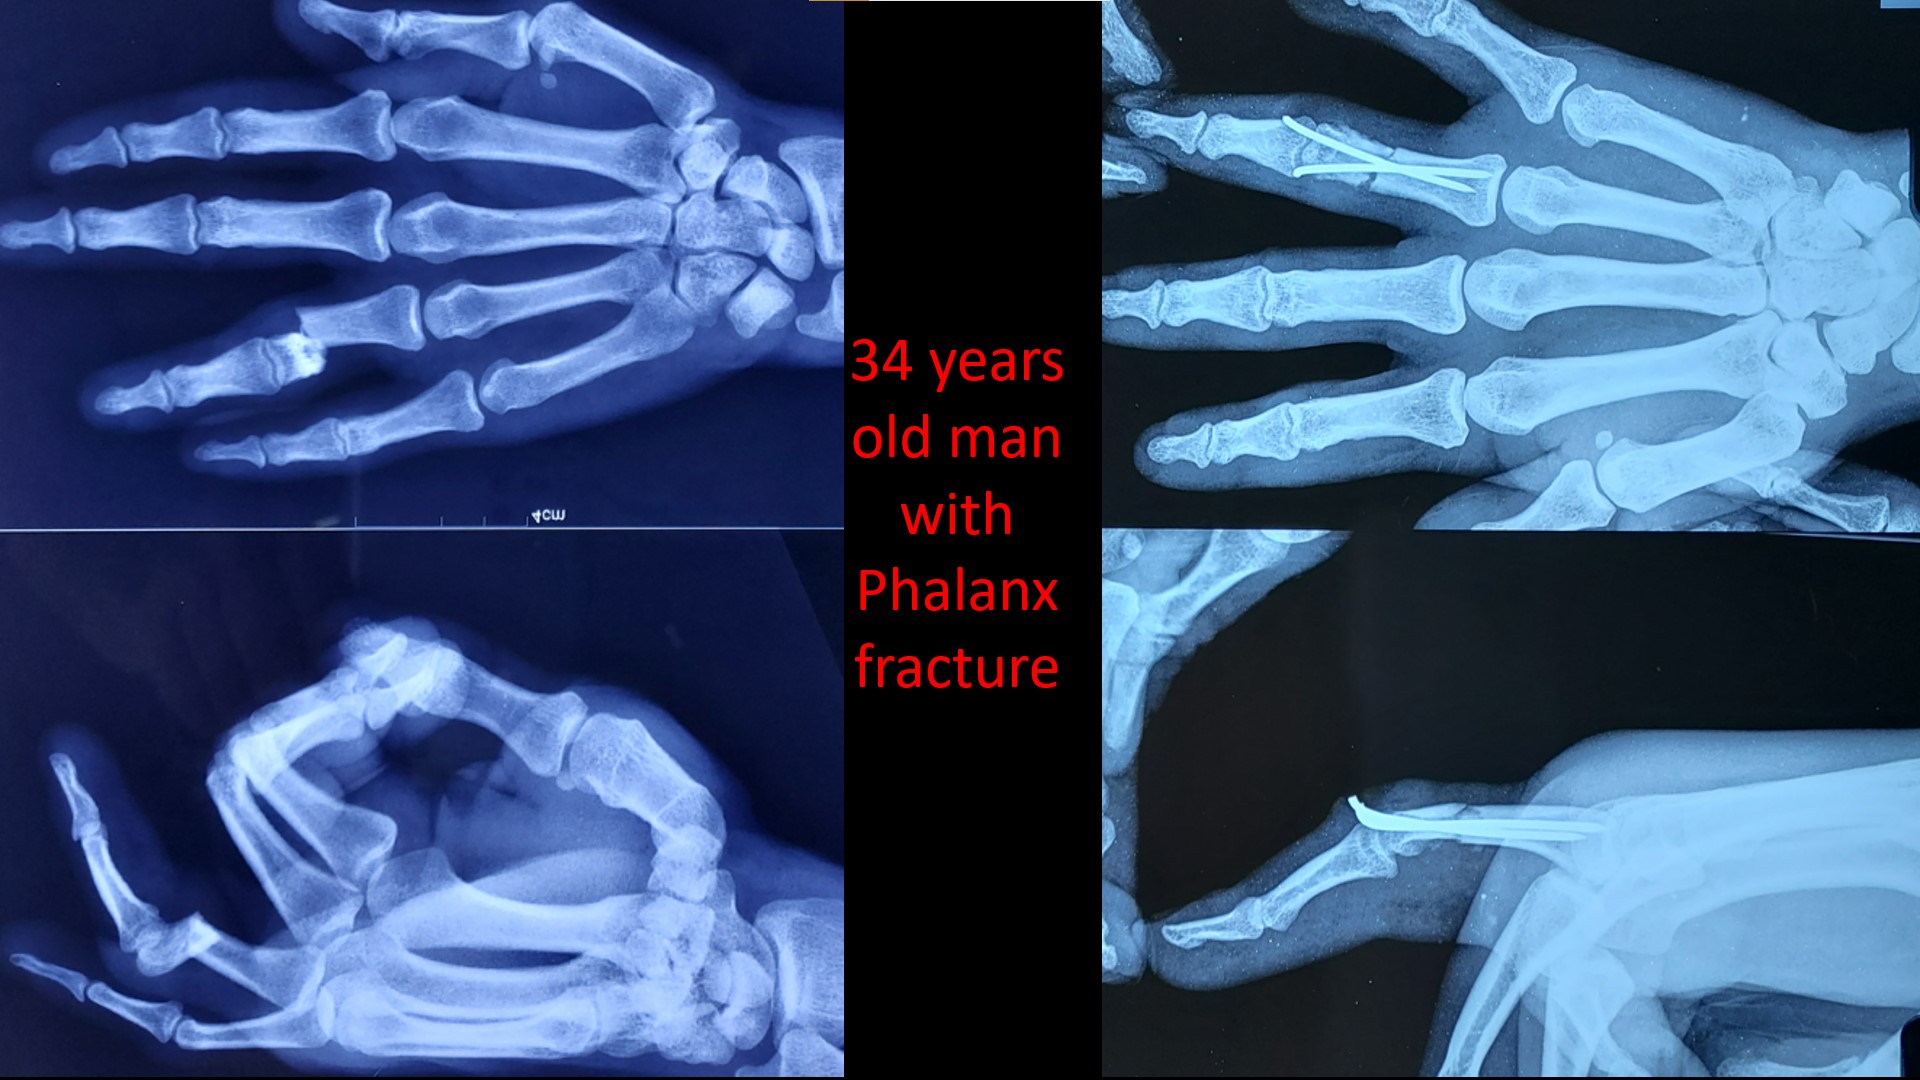

CRPP FRACTRUE PHALANX